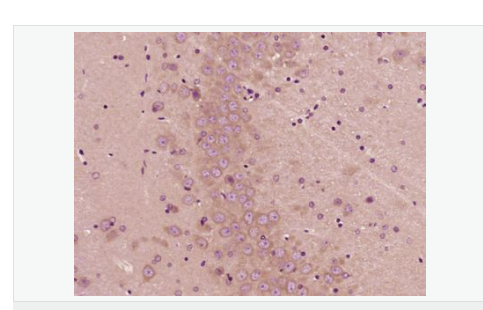

| 產(chǎn)品應用 | ELISA=1:5000-10000 IHC-P=1:100-500 IHC-F=1:100-500 IF=1:100-500 (石蠟切片需做抗原修復) not yet tested in other applications. optimal dilutions/concentrations should be determined by the end user. |

| 產(chǎn)品介紹 | PBR (Peripheral type Benzodiazepine Receptor) is a ubiquitous protein (18 kDa) found in most steroidogenic tissues. It is located primarily in the outer mitochondrial membrane of steroid producing tissues and is found in association with a 34 kDa voltage dependent anion channel protein (VDAC). PBR interacts with some benzodiazepines and has different affinities than its endogenous counterpart. PBR appears to be a key factor in the transport of cholesterol from the outer to the inner mitochondrial membrane to permit the initiation of steroid hormone synthesis. It is thought to be part of the mitochondrial permeability transition pore (PT) and to be involved in apoptosis. It is speculated that patients with congenital lipoid adrenal hyperplasia, who cannot make any steroids, might have a genetic lesion in BZRP. A short form, PBRS is also expressed in the same tissues, but at a level about ten times that of PBR. Function: Responsible for the manifestation of peripheral-type benzodiazepine recognition sites and is most likely to comprise binding domains for benzodiazepines and isoquinoline carboxamides. May play a role in the transport of porphyrins and heme. Plays a role in the transport of cholesterol across mitochondrial membranes in steroidogenic cells. Subcellular Location: Mitochondrion membrane. Tissue Specificity: Found in many tissue types. Expressed at the highest levels under normal conditions in tissues that synthesize steroids. Similarity: Belongs to the TspO/BZRP family. SWISS: B1AH88 Gene ID: 706 Database links: Entrez Gene: 706 Human Entrez Gene: 12257 Mouse Omim: 109610 Human SwissProt: B1AH88 Human SwissProt: P30536 Human SwissProt: P50637 Mouse Unigene: 202 Human Unigene: 1508 Mouse Important Note: This product as supplied is intended for research use only, not for use in human, therapeutic or diagnostic applications. 地西泮結(jié)合抑制因子; DBI能拮抗安定物質(zhì):diazepam與腦突觸膜相結(jié)合 ,故稱之為安定結(jié)合抑制蛋白(DBI),地西泮結(jié)合抑制因子(diazepam binding inhibitor,DBI)具有抑制由葡萄糖誘導的胰島素分泌、促進膽固醇跨線粒體膜轉(zhuǎn)運和調(diào)節(jié)脂肪酸合成與代謝等多種生理功能。 |